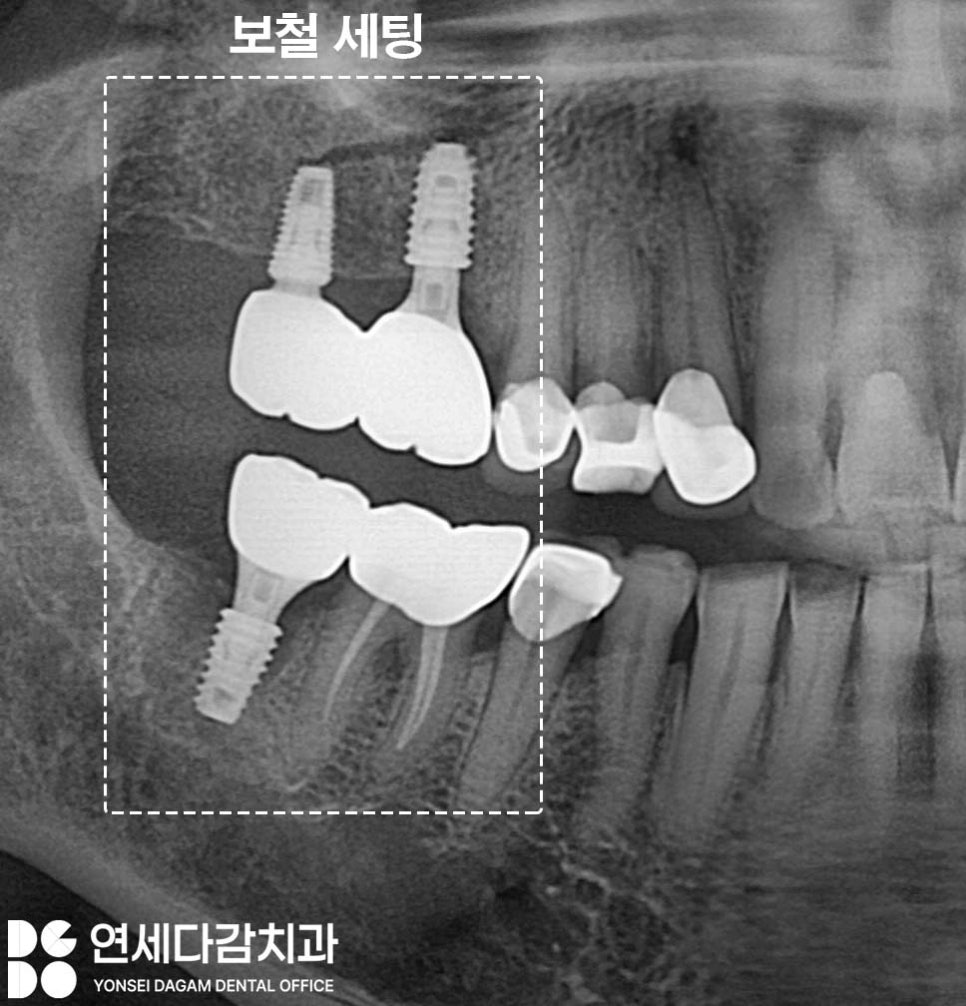

기존에 임플란트가 식립되어 있던 부위의

보철이 부러지는 문제가 생기기도 하죠.

가락시장역 치과 에서는 이런 복합적인

상황을 체계적으로 접근하는 것을

중요시 여깁니다.

파절된 임플란트 보철을 제거하고

임플란트 본체의 상태를 확인해 봤을 때

상부 보철과 연결되는

부위가 부러져 있는 것을

볼 수 있습니다.

치근 우식이 심했던 부위도

발치하여 즉시 임플란트 식립을

시행하게 됩니다.

이렇게 이가 나온 자리에

즉시 식립하면,

발치와의 치유력을 이용하여

더욱 원활한 재생 능력으로

빠른 골 유착을 도모할 수 있습니다.

임플란트와 뼈가 빠르게 유착되어

고정력을 확보하면

나머지 단계도 빠르게 진행되어

최종 단계까지

기간을 단축하게 됩니다.